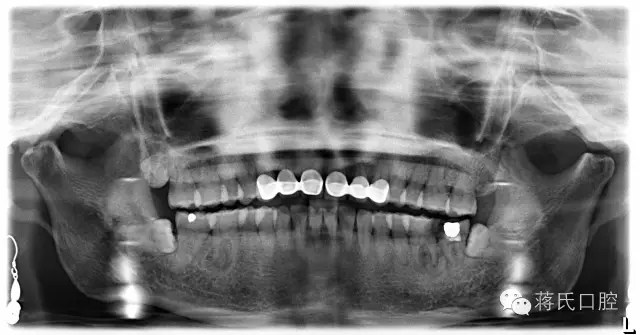

术前检查:全景片显示左下六七残冠并发根尖炎症,骨量丰满、骨高度良好、但因为残冠时间较长,对合牙伸长,咬合距离低,建议患者正畸治疗上牙,但患者拒绝。因为患者是教师职业所以在设计方案及治疗沟通中详细医嘱,每次治疗均经过患者同意后操作。

种植前全景片